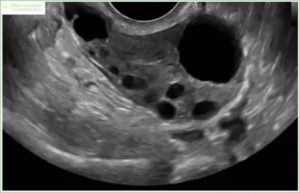

Важную информацию дает ультразвуковое исследование органов малого таза: увеличение объема яичников, увеличение объема стромы яичников (андроген-продуцирующие зоны), множество антральных фолликулов (>10 в каждом яичнике) расположенных диффузно в строме, либо по периферии к строме (I и II тип мультифолликулярных яичников соответственно).